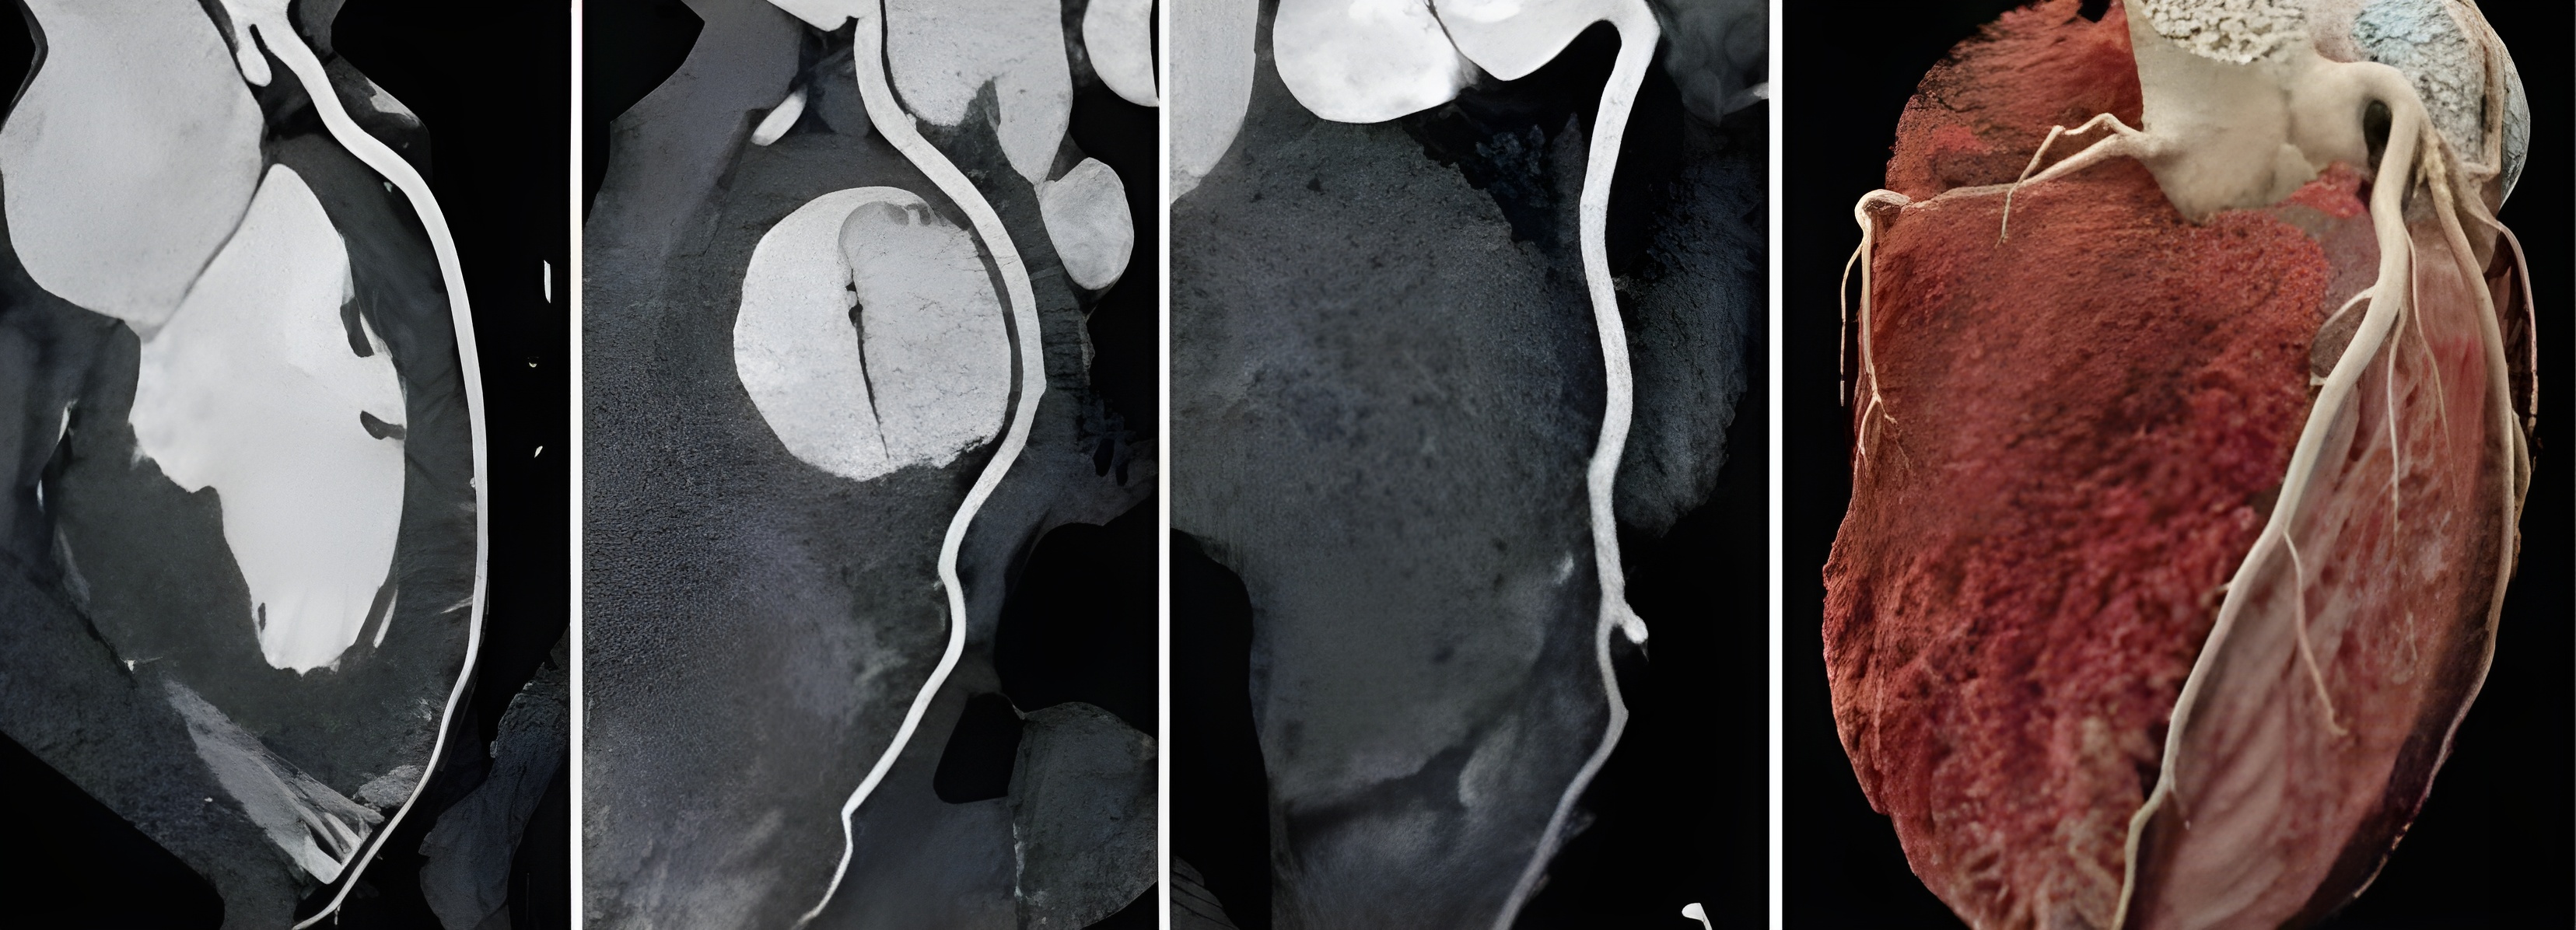

Our 160-slice Coronary CT scanner captures highly detailed, high-resolution images of your heart and blood vessels, helping your doctor see even tiny blockages with great accuracy.

This state-of-the-art cardiac CT system ensures precise imaging of coronary arteries, supporting earlier detection and better management of heart conditions.